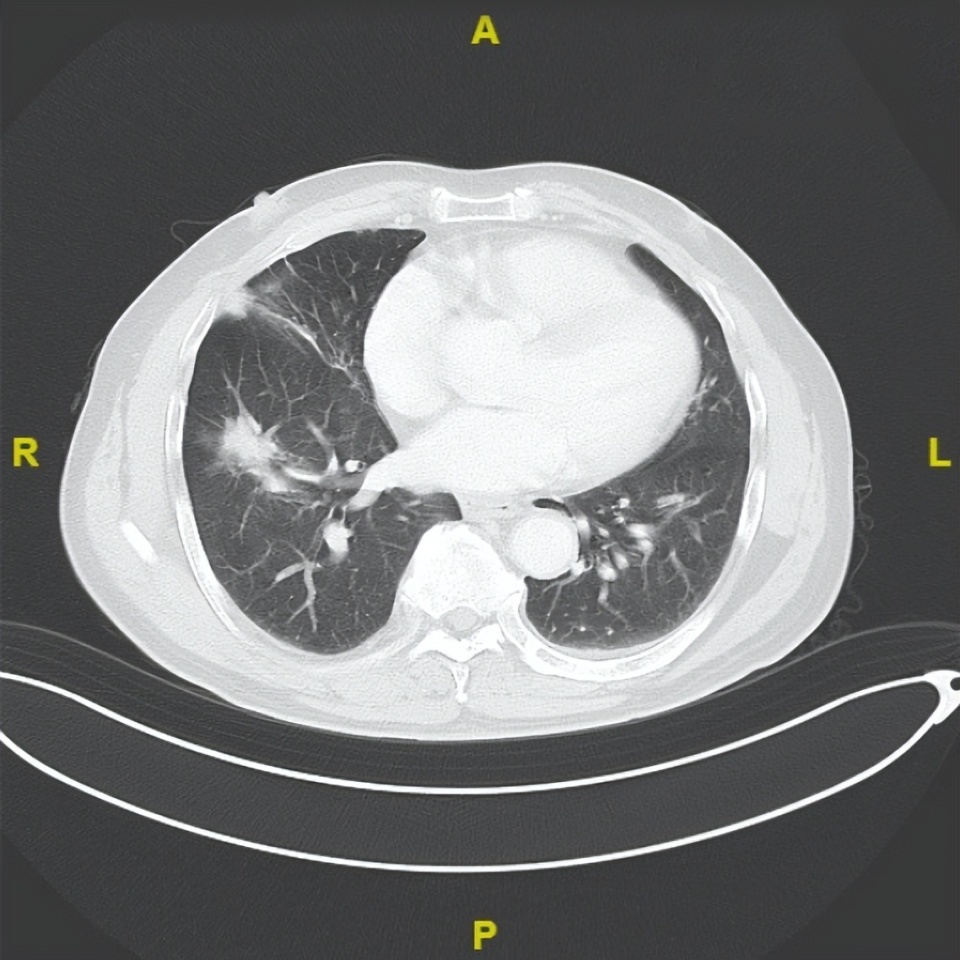

2025年9月24日

△治疗后不同随访时间的胸部及髋关节CT病灶变化